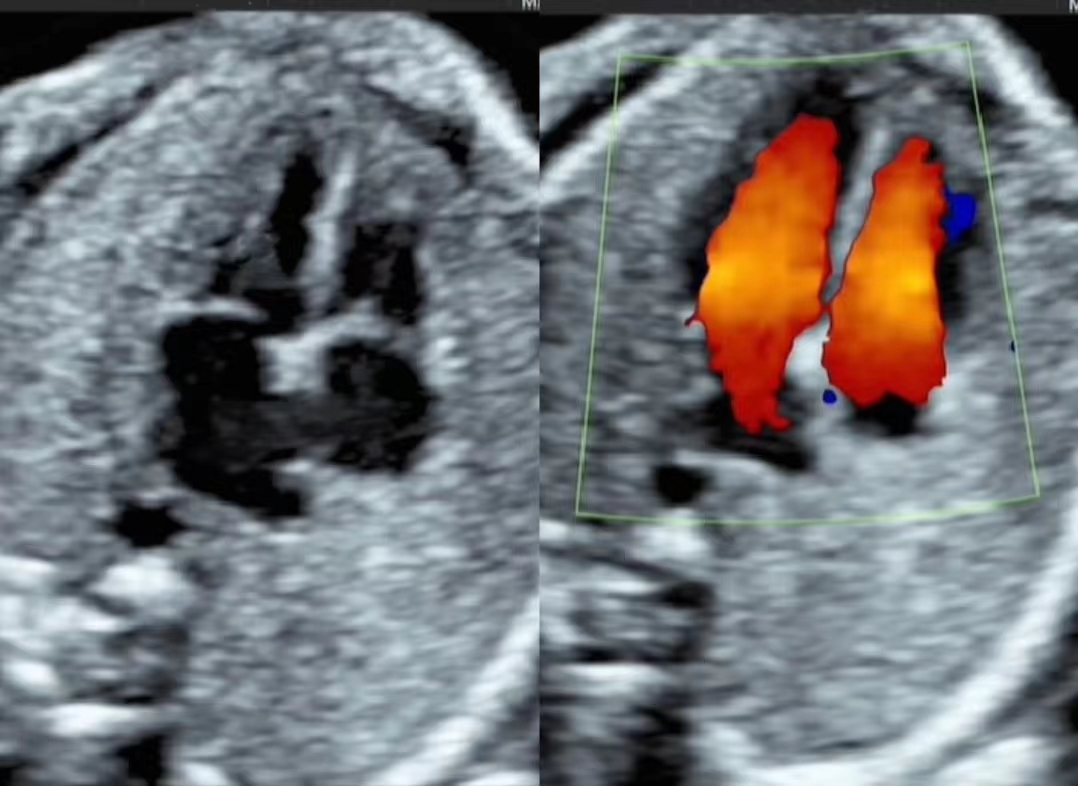

3、明明我做的是“彩超”,为啥您看的图像是“黑白”的?

彩超指的是超声机器具备彩色多普勒成像这个功能,和我们熟知的彩电不同,屏幕中不会一直出现五彩的颜色,只有在医生需要看血流的时候才会显示彩色。同时,彩超的图像分辨率比黑白B超高。因此,彩超比黑白B超功能更全面,图像更清晰。

打个比方,我们的心脏结构就像个四居室的房子:心电图是检测心脏电活动的,相当于检测房子的电路。心脏彩超检查就像医生的眼睛,可以看到你心脏的结构大小搏动及血液流动,相当于检测心脏这个房子的大小门窗墙壁等内部结构。冠状动脉造影是检查冠状动脉内部形态及血流,相当于检测房子的水管通不通。